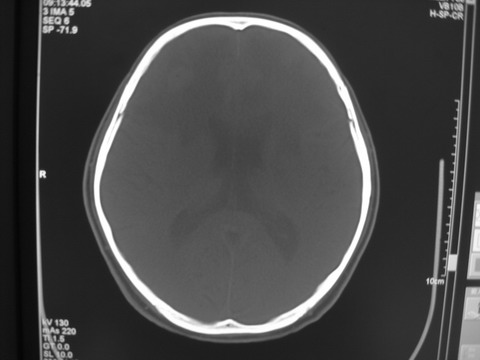

患者 男 69岁 头晕头痛不适

多发病灶,指状水肿,首先诊断转移瘤。

多个结节并周围大面积水肿区,多考虑多发性脑转移瘤

小病灶、大水肿,病灶多发,首先考虑多发转移瘤;建议查原发灶。

额顶叶多发小病灶、大水肿,首先考虑多发转移瘤;建议查原发灶

脑内多发病灶,小病灶,大水肿。

典型转移性肿瘤。

应进一步检查,查找原发病灶。

结果 : 该患者结肠癌病史5年 考虑脑转移